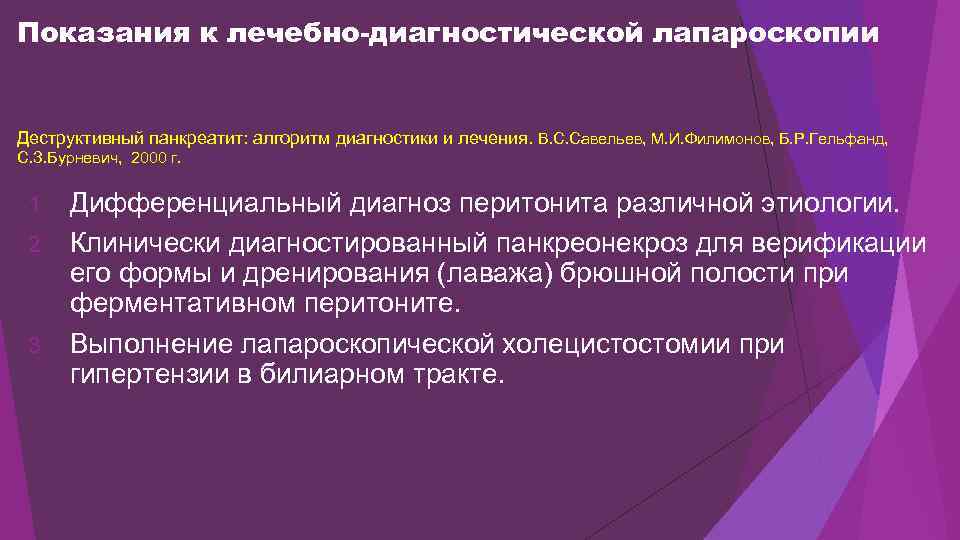

Показания к лечебно-диагностической лапароскопии Деструктивный панкреатит: алгоритм диагностики и лечения. В. С. Савельев, М. И. Филимонов, Б. Р. Гельфанд, С. З. Бурневич, 2000 г. Дифференциальный диагноз перитонита различной этиологии. 2. Клинически диагностированный панкреонекроз для верификации его формы и дренирования (лаважа) брюшной полости при ферментативном перитоните. 3. Выполнение лапароскопической холецистостомии при гипертензии в билиарном тракте. 1.

Показания к лечебно-диагностической лапароскопии Деструктивный панкреатит: алгоритм диагностики и лечения. В. С. Савельев, М. И. Филимонов, Б. Р. Гельфанд, С. З. Бурневич, 2000 г. Дифференциальный диагноз перитонита различной этиологии. 2. Клинически диагностированный панкреонекроз для верификации его формы и дренирования (лаважа) брюшной полости при ферментативном перитоните. 3. Выполнение лапароскопической холецистостомии при гипертензии в билиарном тракте. 1.